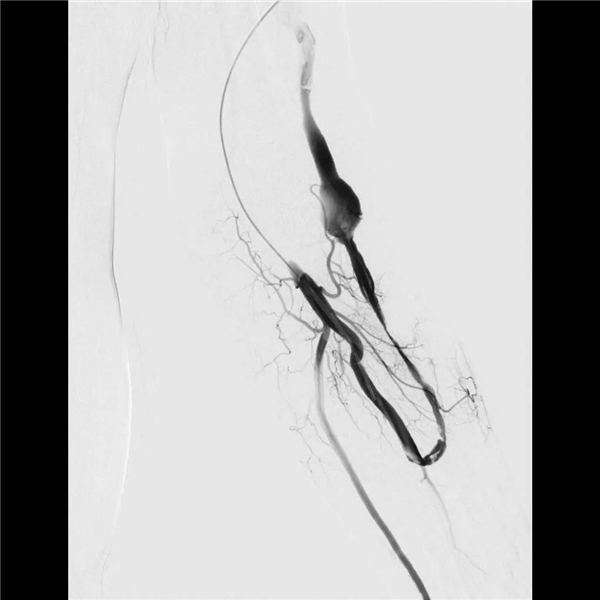

穿刺左侧肱动脉插管后,造影显示(如下图):桡动脉尚通畅,但贵要静脉完全不显影,绿色箭头为闭塞的桡动脉贵要静脉内瘘口,红线为贵要静脉位置。